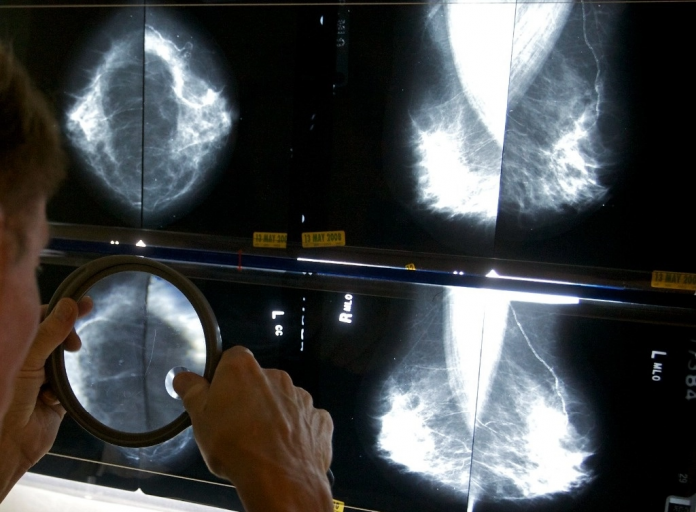

Washington. Las mujeres deben comenzar a hacerse mamografías cada 24 meses a partir de los 40 años para reducir el riesgo de morir de esta enfermedad, recomendó este martes el Grupo Especial de Servicios Preventivos de Estados Unidos.

Su nueva directriz se basa en una revisión de las pruebas y en un estudio publicado en la revista Journal of the American Medical Association.

«Cada vez son más las mujeres de 40 años que padecen cáncer de mama, y las tasas aumentan aproximadamente 2 por ciento cada año, por lo que esta recomendación supondrá una gran diferencia para las personas de todo el país», declaró en un comunicado la presidenta del grupo de trabajo, Wanda Nicholson. «Empezando a examinar a todas las mujeres a los 40 años, podemos salvar casi 20 por ciento más de vidas», añade.

El cáncer de mama es el segundo más frecuente y la segunda causa de muerte por esta enfermedad entre las mujeres de Estados Unidos, con más de 43 mil fallecimientos en 2023.

Las mujeres afroamericanas tienen 40 por ciento más de probabilidades de morir de esta enfermedad que las blancas, por lo que asegurarse de que empiezan a someterse a pruebas de detección a los 40 años «tiene un beneficio potencial aún mayor» para ellas, afirmó Nicholson.

La nueva recomendación se aplica a casi todas las mujeres, tanto a las que presentan un riesgo medio de cáncer de mama como a las que tienen antecedentes familiares o mamas densas.

Casi la mitad de las mujeres tienen lo que se conoce como tejido mamario denso, que generalmente sólo descubren durante su primera mamografía.

El tejido mamario denso aumenta el riesgo de cáncer de mama y significa que las mamografías pueden no funcionar tan bien para ellas.

«Desgraciadamente, aún no hay pruebas suficientes para que el grupo de trabajo recomiende a favor o en contra de un cribado adicional con ecografía mamaria o resonancia magnética», afirma el organismo, que pide investigar más.

Según el grupo de trabajo, la nueva recomendación se aplica hasta los 74 años, edad a partir de la cual la relación beneficio-riesgo es incierta.

Aunque el cribado es una herramienta poderosa en la lucha contra el cáncer también tiene sus límites, según el grupo de trabajo, que explica por qué no recomienda mamografías anuales.

El exceso de pruebas aumenta el número de daños, como los falsos positivos o recibir un tratamiento que no era necesario.